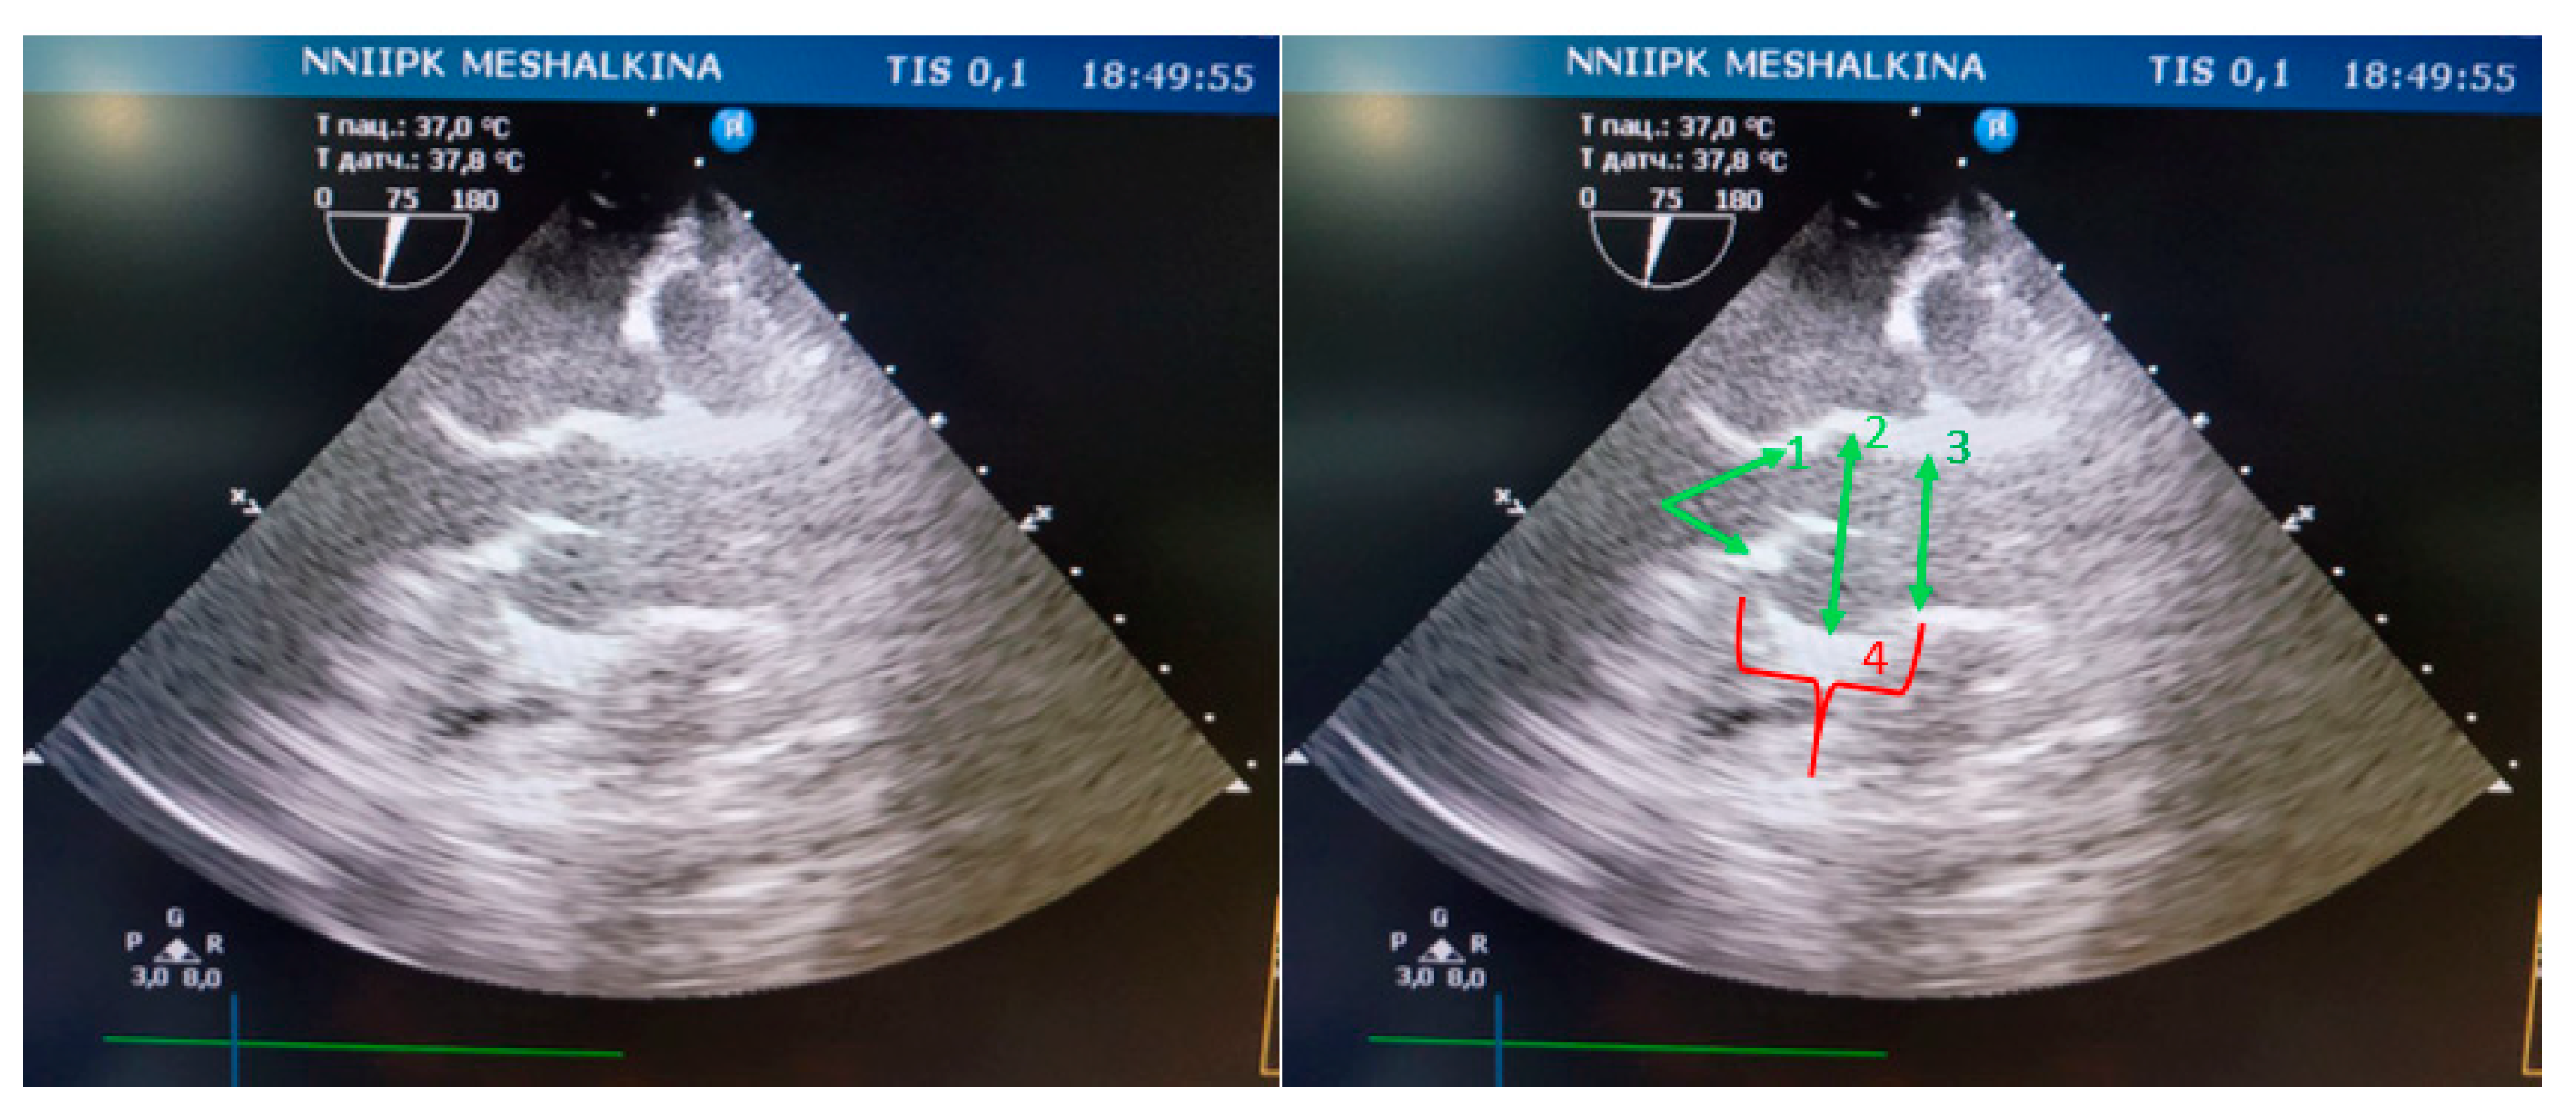

In all animals structures such as the fibrous ring of the aortic valve, the sinus of the Valsalva, and the sinotubular junction were clearly identified by transesophageal echocardiography (Figure 4).

Figure 4. Visualization of the aortic root in mini pigs on TЕE : 1- fibrous ring of the aortic valve; 2- sinus Valsalva; 3- sinotubular junction; 4- height of the aortic root.